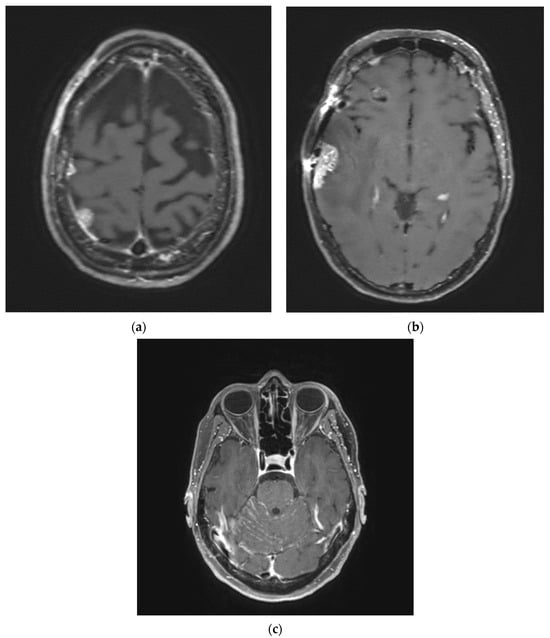

- Sener, U.; Webb, M.; Breen, W.G.; Neth, B.J.; Laack, N.N.; Routman, D.; Brown, P.D.; Mahajan, A.; Frechette, K.; Dudek, A.Z.; et al. Proton Craniospinal Irradiation with Immunotherapy in Two Patients with Leptomeningeal Disease from Melanoma. J. Immunother. Precis. Oncol. 2024, 7, 1–6. [Google Scholar] [CrossRef] [PubMed] [PubMed Central]